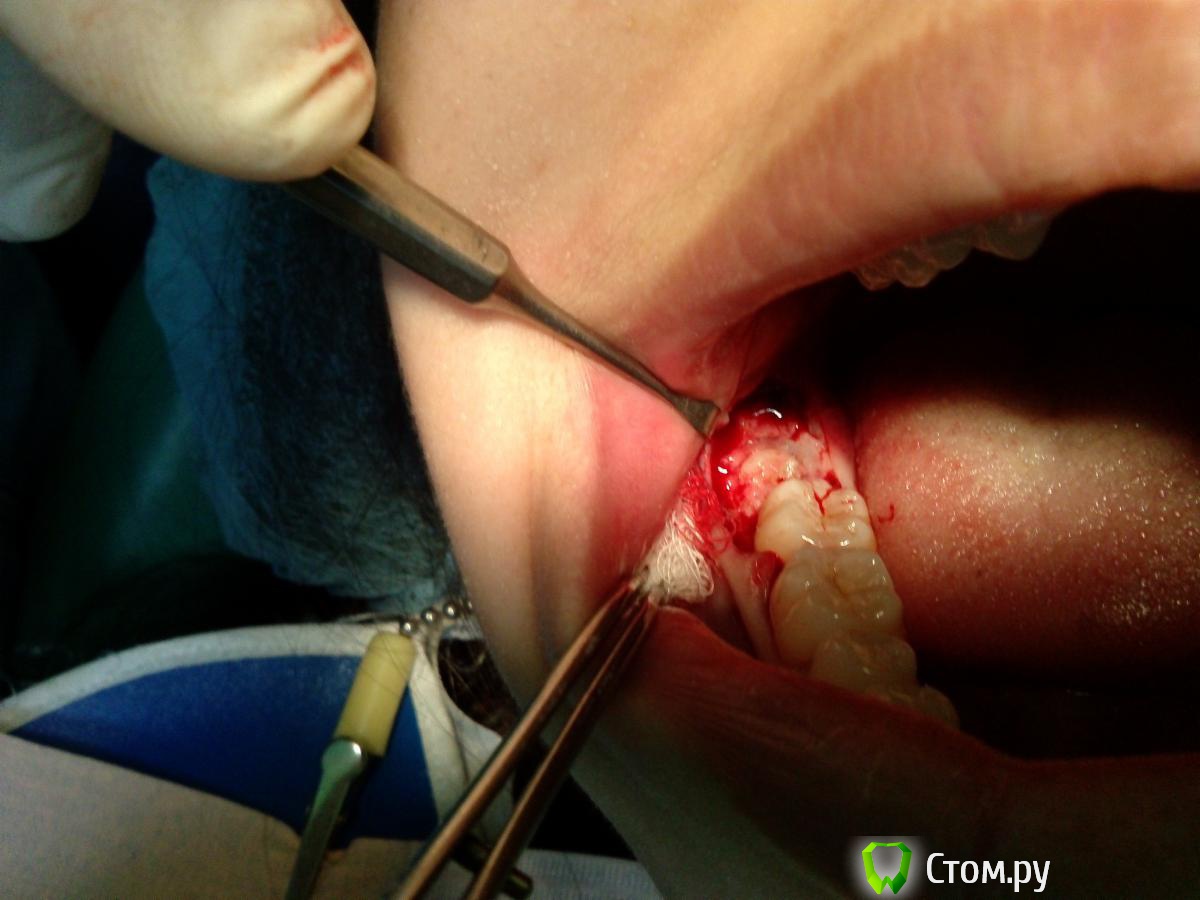

Troy Опубликовано 26 декабря, 2013 Поделиться Опубликовано 26 декабря, 2013 Ретенция, попросил ортодонт 2 Ссылка на комментарий

IvanK Опубликовано 26 декабря, 2013 Автор Поделиться Опубликовано 26 декабря, 2013 Имхо. Можно меньше отслаиваться.Но цель достигнута ) Ссылка на комментарий

Troy Опубликовано 26 декабря, 2013 Поделиться Опубликовано 26 декабря, 2013 Имхо. Можно меньше отслаиваться.Но цель достигнута )Спасибо. Без вертикального разреза меньше не получилось. Ссылка на комментарий